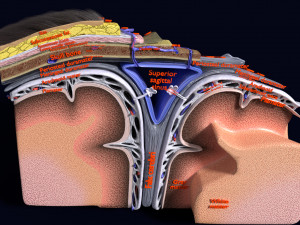

This is a 1:1 scaled model of right breast cut opened in sagittal plane to reveal its internal antomy and histology (schematic). The deeper parts and fascial layers are also depicted to give a very detailed approach to the model. The full layers starting from skin, nipple areola, till intercodtal muscles and ribs are also depicted.